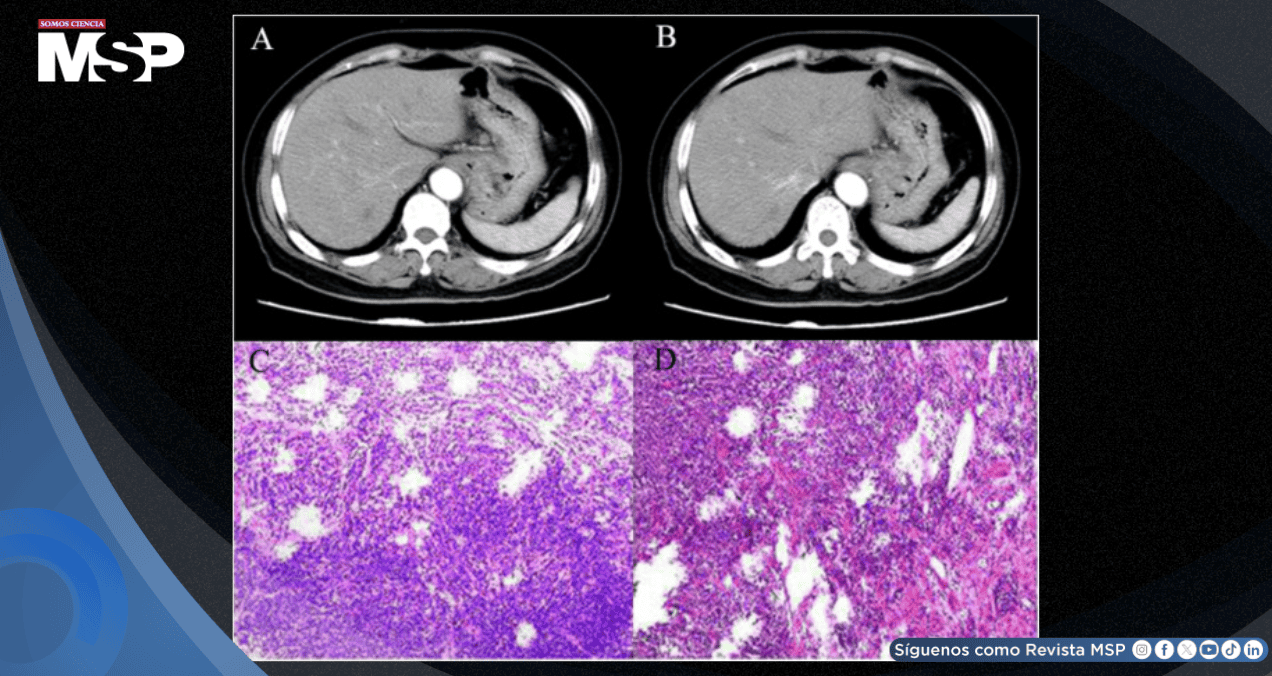

Tras completar la evaluación preoperatoria y descartar contraindicaciones, la paciente fue sometida a una intervención quirúrgica. La pieza quirúrgica extraída permitió una descripción macroscópica detallada: en la pequeña curvatura del estómago, a 1 cm del extremo superior, se identificó una masa ulcerada de 4.5 x 4 cm, con una superficie de característica coloración negruzca.

El análisis histopatológico definitivo confirmó el diagnóstico de melanoma maligno. La inmunohistoquímica, una técnica esencial para tipificar los tumores, mostró un patrón característico: positividad para los marcadores S-100, HMB-45 y Vimentina (Vim+), típicos del melanoma.

El índice de proliferación celular Ki-67 era alto (aproximadamente 70%), indicando una alta agresividad tumoral. Los estudios de patogénesis molecular no mostraron mutaciones significativas en los genes HER-2 o B-RAF dentro del rango analizado.